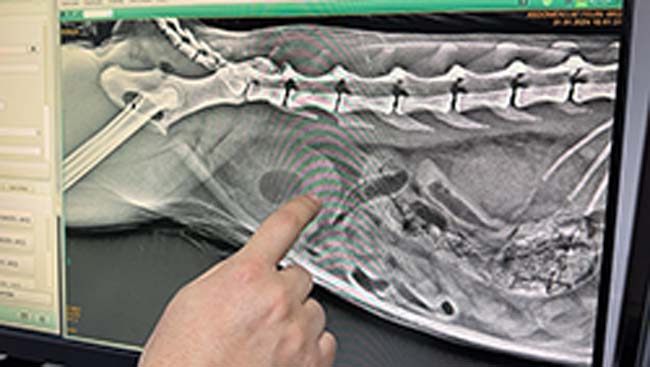

Zonguldak'ta sahibinin idrar yapamama şikayetiyle veterinere getirdiği kedinin idrar kesesinden çok sayıda kristal çıktı. Zorlu bir ameliyat süreci yaşadıklarını ifade eden Veteriner Hekim Gökmen Koç, kısırlaştırılan her 10 vakanın 4'ünde bu şikayetlerin görüldüğünü belirterek, "Böyle durumlarda ilk aklımıza gelen ve hasta sahibinden gelen ilk şikayet, 'Hocam acaba bu hayvan kabız mı oldu?' oluyor. 'Kumuna gidiyor, saatlerce orada kalıyor' şikayeti ile geliyorlar. Yaptığımız tetkiklerde idrar kesesinin dolu olduğunu gördük. Aldığımız röntgen ve ultrason görüntülerinde de bunu pekiştirdik. Hemen anestezi altında müdahale edildi. Ortalama yarım saat, 40 dakika o kristallerin atılmasını sağlamaya çalıştık. Zordu, güçtü. Meslek hayatımdaki en zor sondalamalardan biriydi. Burada idrar yolunu açmadan sondalamaya çalışmak kesinlikle çok daha kötü sonuçlanıyor. İdrar kesesini de yıkadıktan sonra amacımız şu anda idrar kesesinde biriken bütün tuzları eritmek."